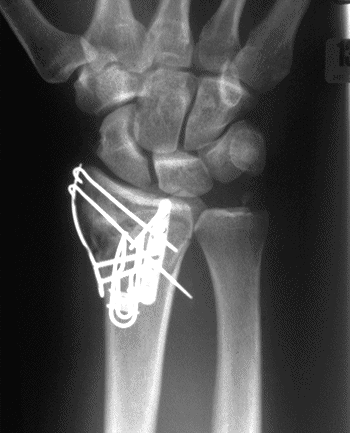

Case 4 Postop